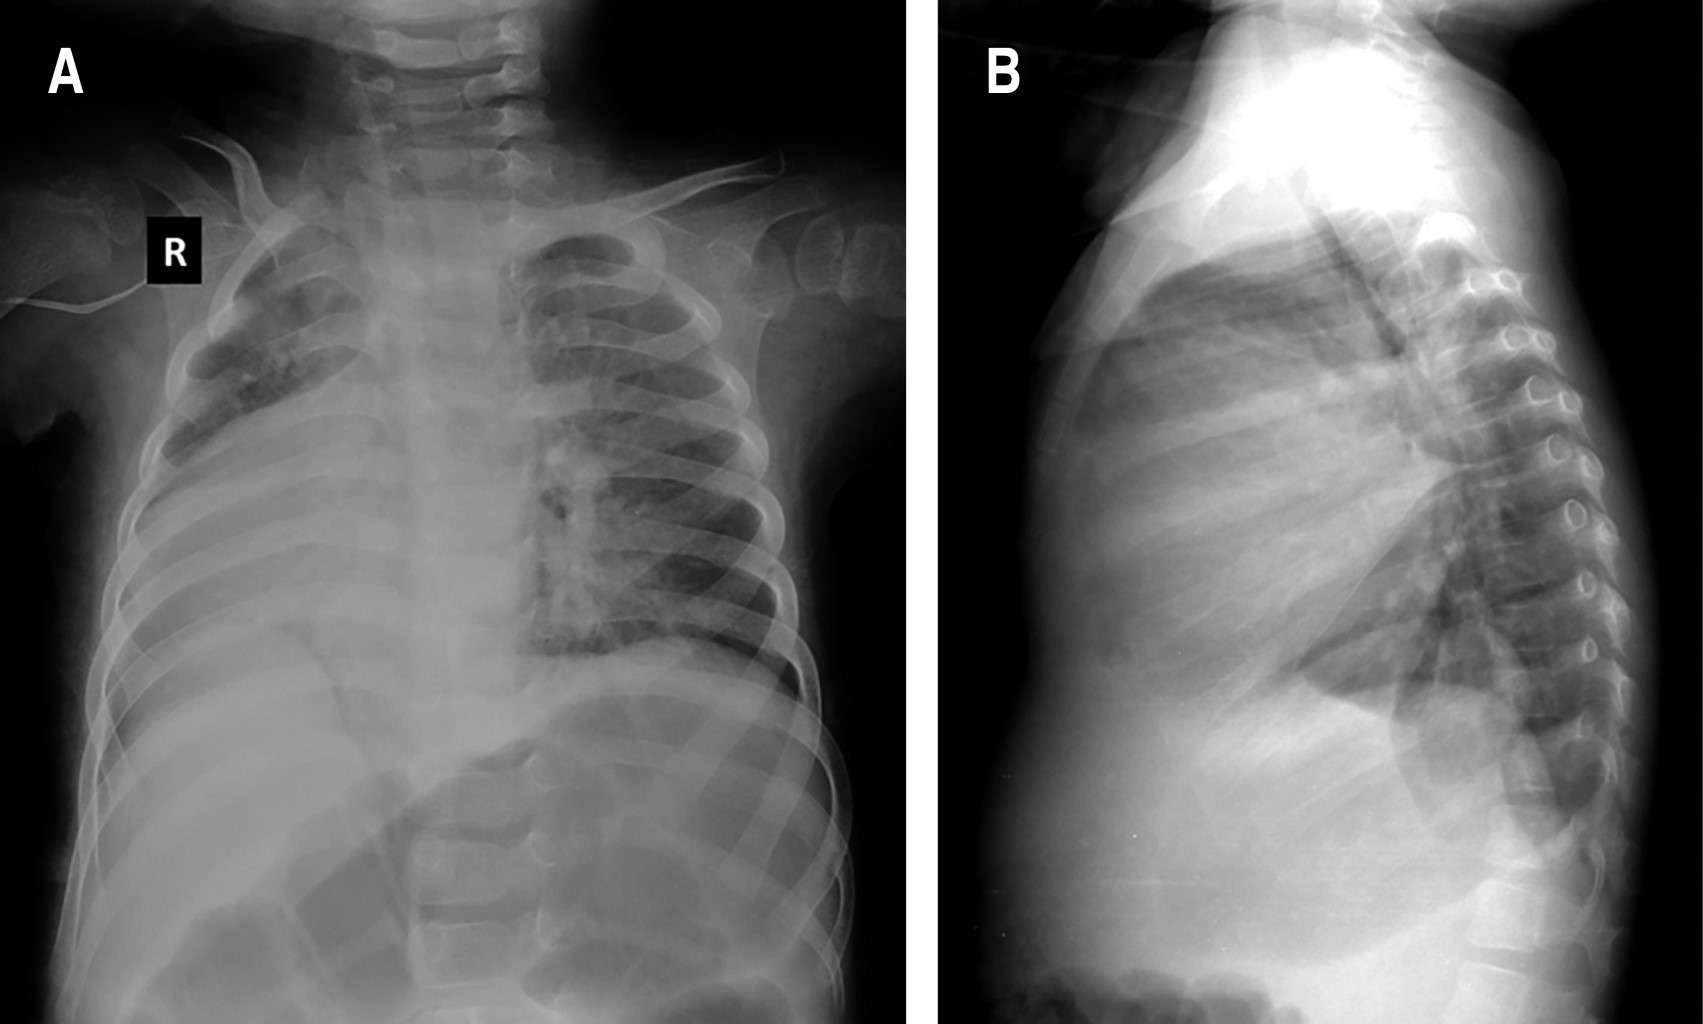

A los dos meses de edad, cardiología pediátrica mediante estudios de imagen estableció que presentaba dextrocardia y persistencia de conducto arterioso (Figura 1). En cuanto a su desarrollo se determinó retraso psicomotor grave, ya que a los dos años empezó la emisión de sonidos guturales y a sonreír a los tres. En tomografía de cráneo no se detectaron malformaciones del sistema nervioso central. Sin embargo, poco tiempo después aparecieron crisis convulsivas parciales complejas que fueron controladas con clonazepam; inicialmente eran dos crisis por semana, pero fueron disminuyendo a una por mes. En electroencefalograma se reportaron cambios epilépticos difusos. Por oftalmoscopía se evidenciaron cambios atróficos en ambos nervios ópticos; mientras que en potenciales evocados de tallo cerebral se identificó sordera moderada en oído derecho.

Un defecto que destacar, que estuvo presente en nuestro caso, pero es poco frecuente, es la dextrocardia, la cual se ha descrito previamente en dos publicaciones.20,21 Uno de ellos corresponde a la paciente con mayor tiempo de supervivencia reportada, una mujer afroamericana de 32 años, mientras el otro también es una mujer de 19 años. Señalamos que se han descrito diferentes defectos cardiacos congénitos, en más de 70% de los pacientes.5,13,22,23

Figura 1